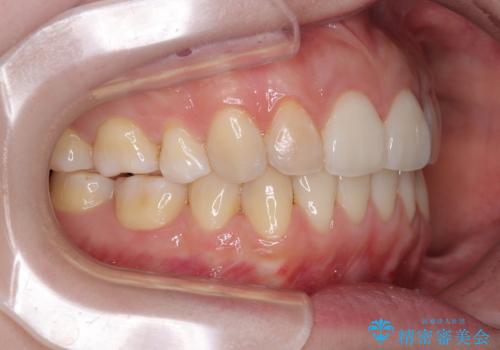

後戻りをインビザラインでスッキリした口元に

- 高校生の時に矯正治療を行ったものの、後取りをしてしまったとのことで来院された患者様です。

マウスピースでもワイヤー矯正でも対応可能でしたが、再度ワイヤーは装着したくないとのことでインビザラインにて矯正治療を行うこととしました。

舌の突出癖が原因で後戻りをしたため、舌のトレーニングをしっかりと行っていただき、口元の突出感を改善することができました。

インビザラインの装着時間が守れず、1年強で終わる予定でしたが、4年間を要することとなりました。